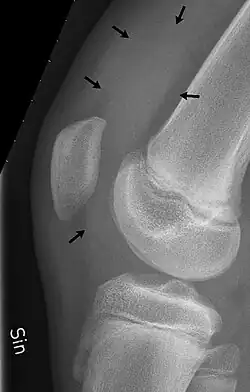

X-Ray

An X-ray may be recommended by your provider as a way to obtain a 2-dimensional image to visualize the joint in question. In the presence of trauma an X-ray can be especially useful to verify that there is no break, dislocation, or deformity. In an atraumatic knee, an X-Ray can be used to identify or rule out other causes of a knee infusion including some inflammatory or age-related causes.